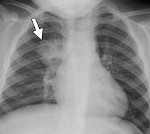

Лечение гнойной (абсцедирующей, септической) пневмонии

Гнойная пневмония — это не болезнь сама по себе, а осложнение первичной пневмонии. Сам процесс характеризуется ограниченными гнойно-деструктивными изменениями легочной ткани, т.е. образованием абсцесса. При неблагоприятном течении может перерасти в септическую пневмонию. В МКБ-10 гнойная пневмония не выделяется как отдельное заболевание, но может быть классифицирована как «пневмония без определенного возбудителя» (J18). Этиология абсцедирующего воспаления легких …